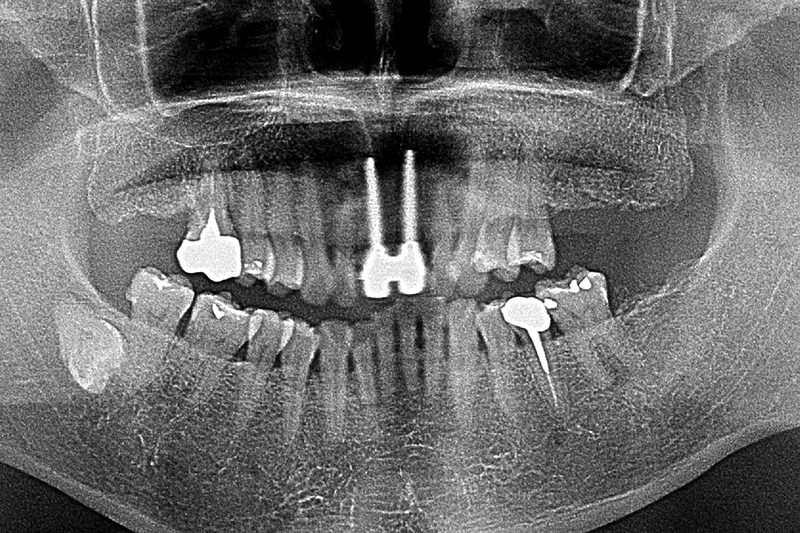

初診環口X光片檢測可見植體的角度位置都不理想,齒槽骨有吸收的現象。建議患者先接受牙周病的第一階段治療,進行感染控制

環口X光片術前

環口x光片術後